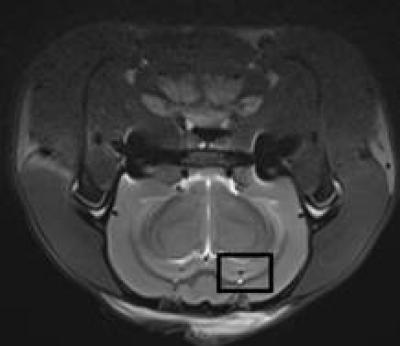

Magnetic resonance spectroscopy can quantitatively analyze in vivo abnormalities of biochemical metabolism within brain tissue in a noninvasive and non-radioactive manner. Compared with 3.0T magnetic resonance spectroscopy, high-field magnetic resonance spectroscopy (≥ 7.0T) exhibits high spatial resolution and density resolution, microscopic imaging of the living body, and obtains both high scanning resolution and result precision within a shorter scan time, thus providing a higher value in clinical diagnosis. In a recent study reported in the Neural Regeneration Research (Vol. 9, No. 4, 2014), 7.0T magnetic resonance spectroscopy showed that in the hippocampus of Alzheimer's disease rats, the N-acetylaspartate wave crest was reduced, and the creatine and choline wave crest was elevated. This finding was further supported by hematoxylin-eosin staining, which showed a loss of hippocampal neurons and more glial cells. Moreover, electron microscopy showed neuronal shrinkage and mitochondrial rupture, and scanning electron microscopy revealed small size hippocampal synaptic vesicles, incomplete synaptic structure, and reduced number. Overall, these findings from Lei Zhang and co-workers from Beijing Tiantan Hospital Affiliated to Capital Medical University in China revealed that 7.0T high-feld nuclear magnetic resonance spectroscopy detected the lesions and functional changes in hippocampal neurons of Alzheimer's disease rats in vivo, allowing the possibility for assessing the success rate and grading of the animal model of Alzheimer's disease.

Article: " 7.0T nuclear magnetic resonance evaluation of the amyloid beta (1) animal model of Alzheimer's disease: comparison of cytology verifcation," by Lei Zhang1, Shuai Dong2, Guixiang Zhao3, Yu Ma4 (1 MR Neuroradiology Room, Beijing Tiantan Hospital Affliated to Capital Medical University, Beijing, China; 2 Department of Neurology, Sixth People's Hospital of Jinan, Jinan, Shandong Province, China; 3 Department of Rehabilitation Medicine, Sixth People's Hospital of Jinan, Jinan, Shandong Province, China; 4 Tsinghua University Yuquan Hospital, Beijing, China) Zhang L, Dong S, Zhao GX, Ma Y. 7.0T nuclear magnetic resonance evaluation of the amyloid beta (1) animal model of Alzheimer's disease: comparison of cytology verification. Neural Regen Res . 2014;9(4):430-435.